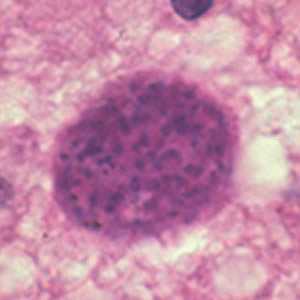

Toxoplasma gondii cyst in brain tissue.

Figure A: Toxoplasma gondii cyst in brain tissue stained with hematoxylin and eosin.

Figure B: Toxoplasma gondii cyst stained with hematoxylin and eosin.